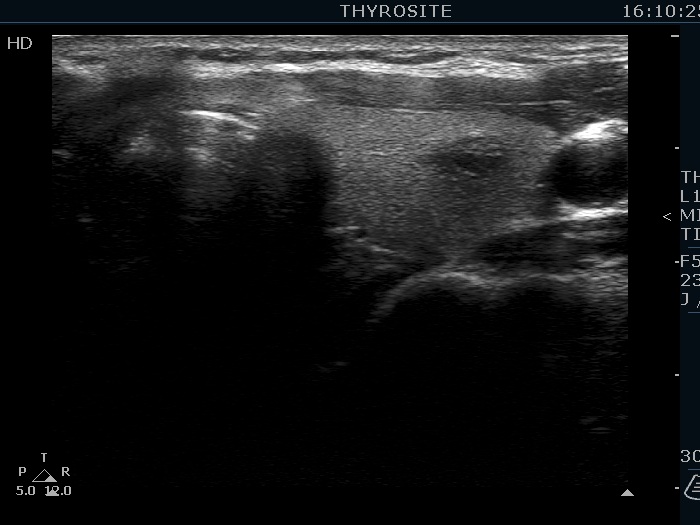

Ultrasonography. The thyroid was echonormal. There were several hypoechoic nodules in the left lobe. The middle one had back wall cystic figures. There were 3 or four discrete, deeply hypoechoic lesions above and lateral to the left lobe in the neck. One of them presented with a hilum-like figure while the others lacked hilum.

Histopathology disclosed benign hyperplastic nodules and reactive type lymph nodes.